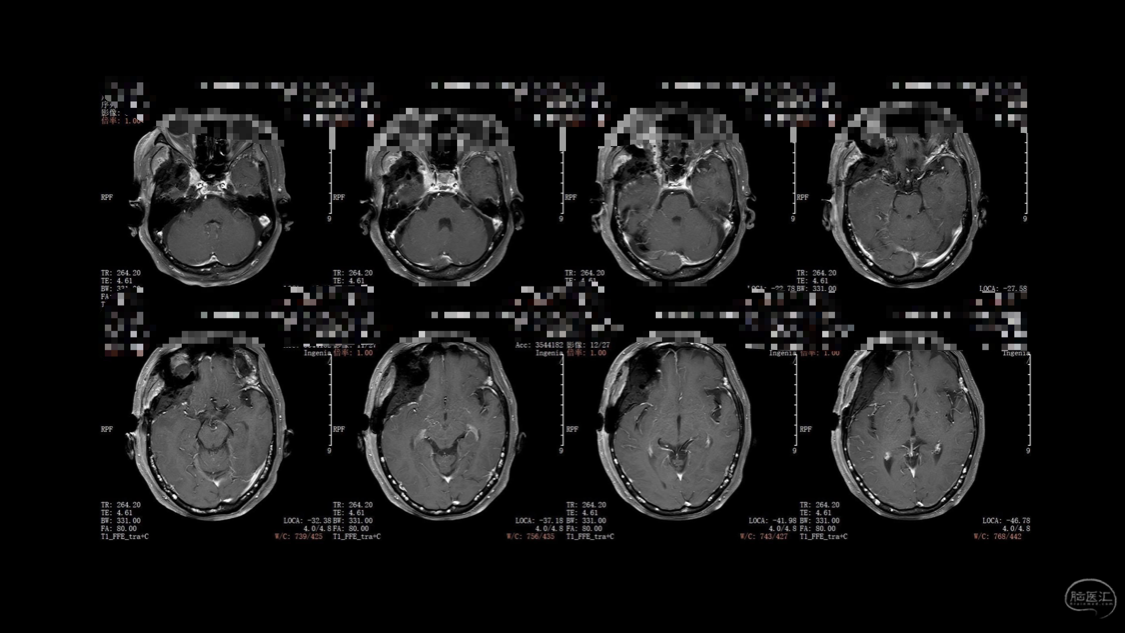

陈保东教授手术作品-右眶内及海绵窦旁孤立性纤维瘤